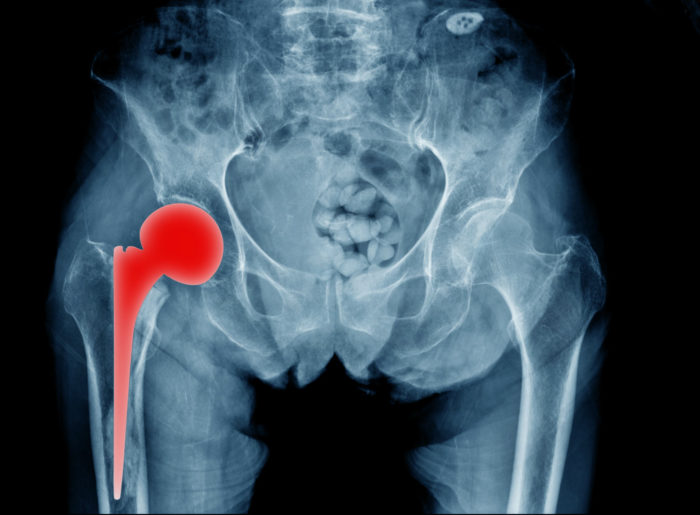

Stryker Hip Replacement Recall List . Please inform users of this urgent. Learn about the latest developments in stryker hip replacement lawsuits involving lfit v40, rejuvenate, abg ii and tritanium devices. Find out the causes, complications, settlements and lawsuits related to the recalls. Please contact your local sales office or your stryker sales representative directly for product replacement and inventory. On 10/15/2021, stryker issued urgent medical device recall notices to customers. Learn about the stryker hip implant recalls involving rejuvenate, abg ii, lfit v40 and accolade tmzf devices. The aaos device recall dashboard provides orthopaedic surgeons with timely recall information that will protect the health and well. Find out if you qualify to file a claim and what injuries are named in the lawsuits. The fda recommends not using or implanting the synovo total hip system, including resurfacing implants, after 2019 due to. Learn about the hip replacement lawsuits filed against stryker and other device makers for complications such as metal poisoning, infection, and nerve damage.

The fda recommends not using or implanting the synovo total hip system, including resurfacing implants, after 2019 due to. Learn about the stryker hip implant recalls involving rejuvenate, abg ii, lfit v40 and accolade tmzf devices. On 10/15/2021, stryker issued urgent medical device recall notices to customers. Find out if you qualify to file a claim and what injuries are named in the lawsuits. Learn about the latest developments in stryker hip replacement lawsuits involving lfit v40, rejuvenate, abg ii and tritanium devices. Please contact your local sales office or your stryker sales representative directly for product replacement and inventory. Please inform users of this urgent. The aaos device recall dashboard provides orthopaedic surgeons with timely recall information that will protect the health and well. Learn about the hip replacement lawsuits filed against stryker and other device makers for complications such as metal poisoning, infection, and nerve damage. Find out the causes, complications, settlements and lawsuits related to the recalls.

Stryker Hip Replacement Recall List Learn about the stryker hip implant recalls involving rejuvenate, abg ii, lfit v40 and accolade tmzf devices. Learn about the hip replacement lawsuits filed against stryker and other device makers for complications such as metal poisoning, infection, and nerve damage. Please inform users of this urgent. Find out the causes, complications, settlements and lawsuits related to the recalls. On 10/15/2021, stryker issued urgent medical device recall notices to customers. The aaos device recall dashboard provides orthopaedic surgeons with timely recall information that will protect the health and well. Learn about the stryker hip implant recalls involving rejuvenate, abg ii, lfit v40 and accolade tmzf devices. Find out if you qualify to file a claim and what injuries are named in the lawsuits. Please contact your local sales office or your stryker sales representative directly for product replacement and inventory. The fda recommends not using or implanting the synovo total hip system, including resurfacing implants, after 2019 due to. Learn about the latest developments in stryker hip replacement lawsuits involving lfit v40, rejuvenate, abg ii and tritanium devices.